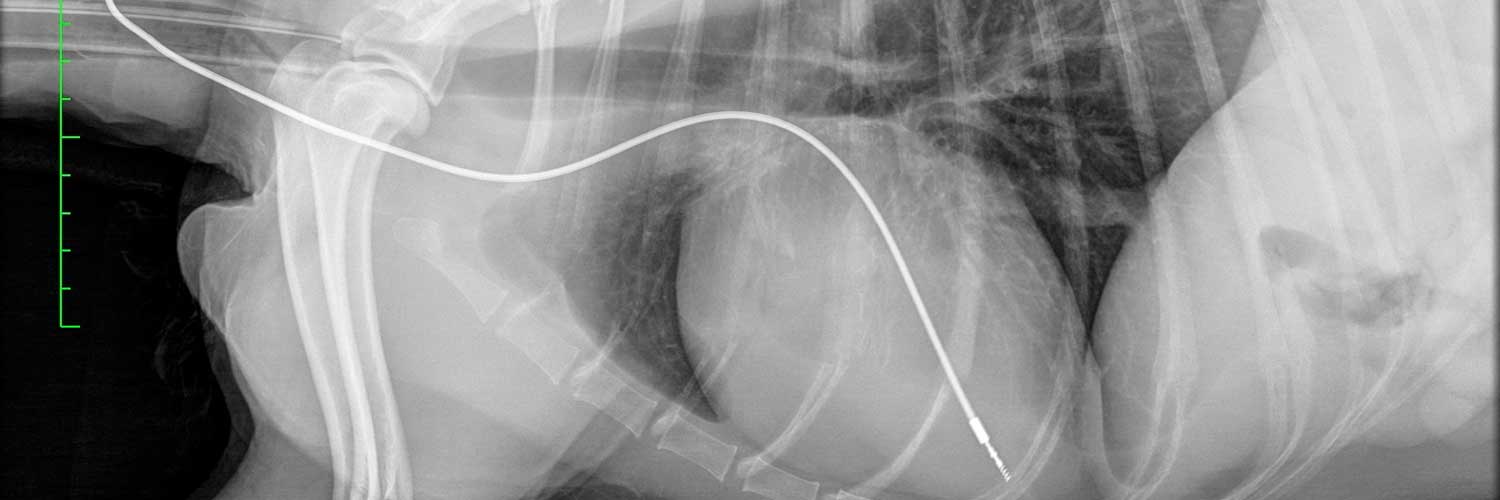

Disponemos de un equipamiento puntero para la investigación de problemas cardíacos y respiratorios. Entre estos equipos disponemos de ecocardiografía (GE e95, incluyendo 4D y ecocardiografía transesofágica), ECG digital de 12 derivaciones, monitor y software avanzado de Holter, programador de marcapasos, fluoroscopia de alta calidad, inyector de presión y un esterilizador especifico de gases fríos que nos permite la realización de angiografías e intervencionismo con todas las garantías; también disponemos de TAC Siemens y una amplia gama de endoscopios de alta calidad de todos los tamaños para la investigación adecuada de problemas respiratorios.

De manera rutinaria se realizan investigaciones en pacientes en los que se han detectado signos tales como: soplos, arritmias, tos, dificultades respiratorias o desfallecimientos; y se tratan multitud de enfermedades congénitas y adquiridas entre las que destacan terapias intervencionistas como el cierre del conducto arterioso persistente, la implantación de marcapasos o las valvuloplastias pulmonar y aórtica.